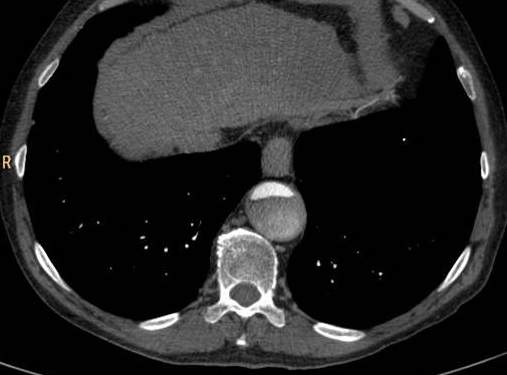

Fig.1., 2.: Hypertrophic obstructive cardiomyopathy: Longitudinal and short axis slices of delayed enhancement of contrast material in the heart: pathologic enhancement is visible in the myocardium in the asymmetrically thickened left ventricular wall, referring to a degenerative-fibrotic process.